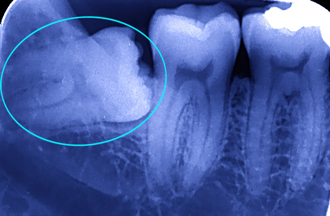

レントゲンで確認すると、親知らずの歯は、真横向き=写真=に生えていました。私は「この抜歯は今すぐには…」と考え、日を改めて抜歯をさせて頂くことになりました。